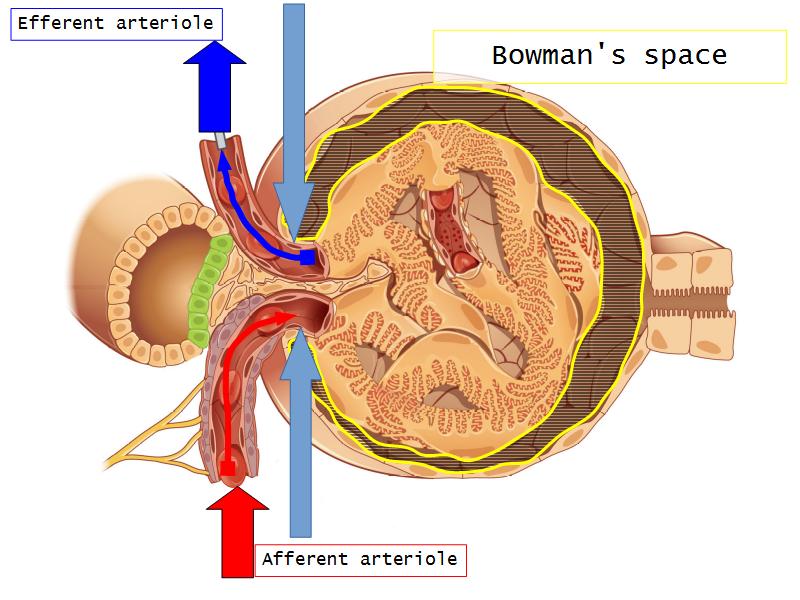

- The renal corpuscle

- Make an annotated diagram of a nephron, including the juxtaglomerular apparatus. Indicate the flow of blood and water in each part, and how solutes are filtered, secreted and reabsorbed.